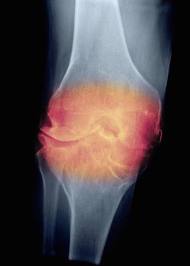

La artrosis es una enfermedad

degenerativa que provoca la pérdida del cartílago que recubre las

superficies articulares. Investigadores desarrollaron una técnica

por medio de la cual se regeneran los cartílagos de las

articulaciones